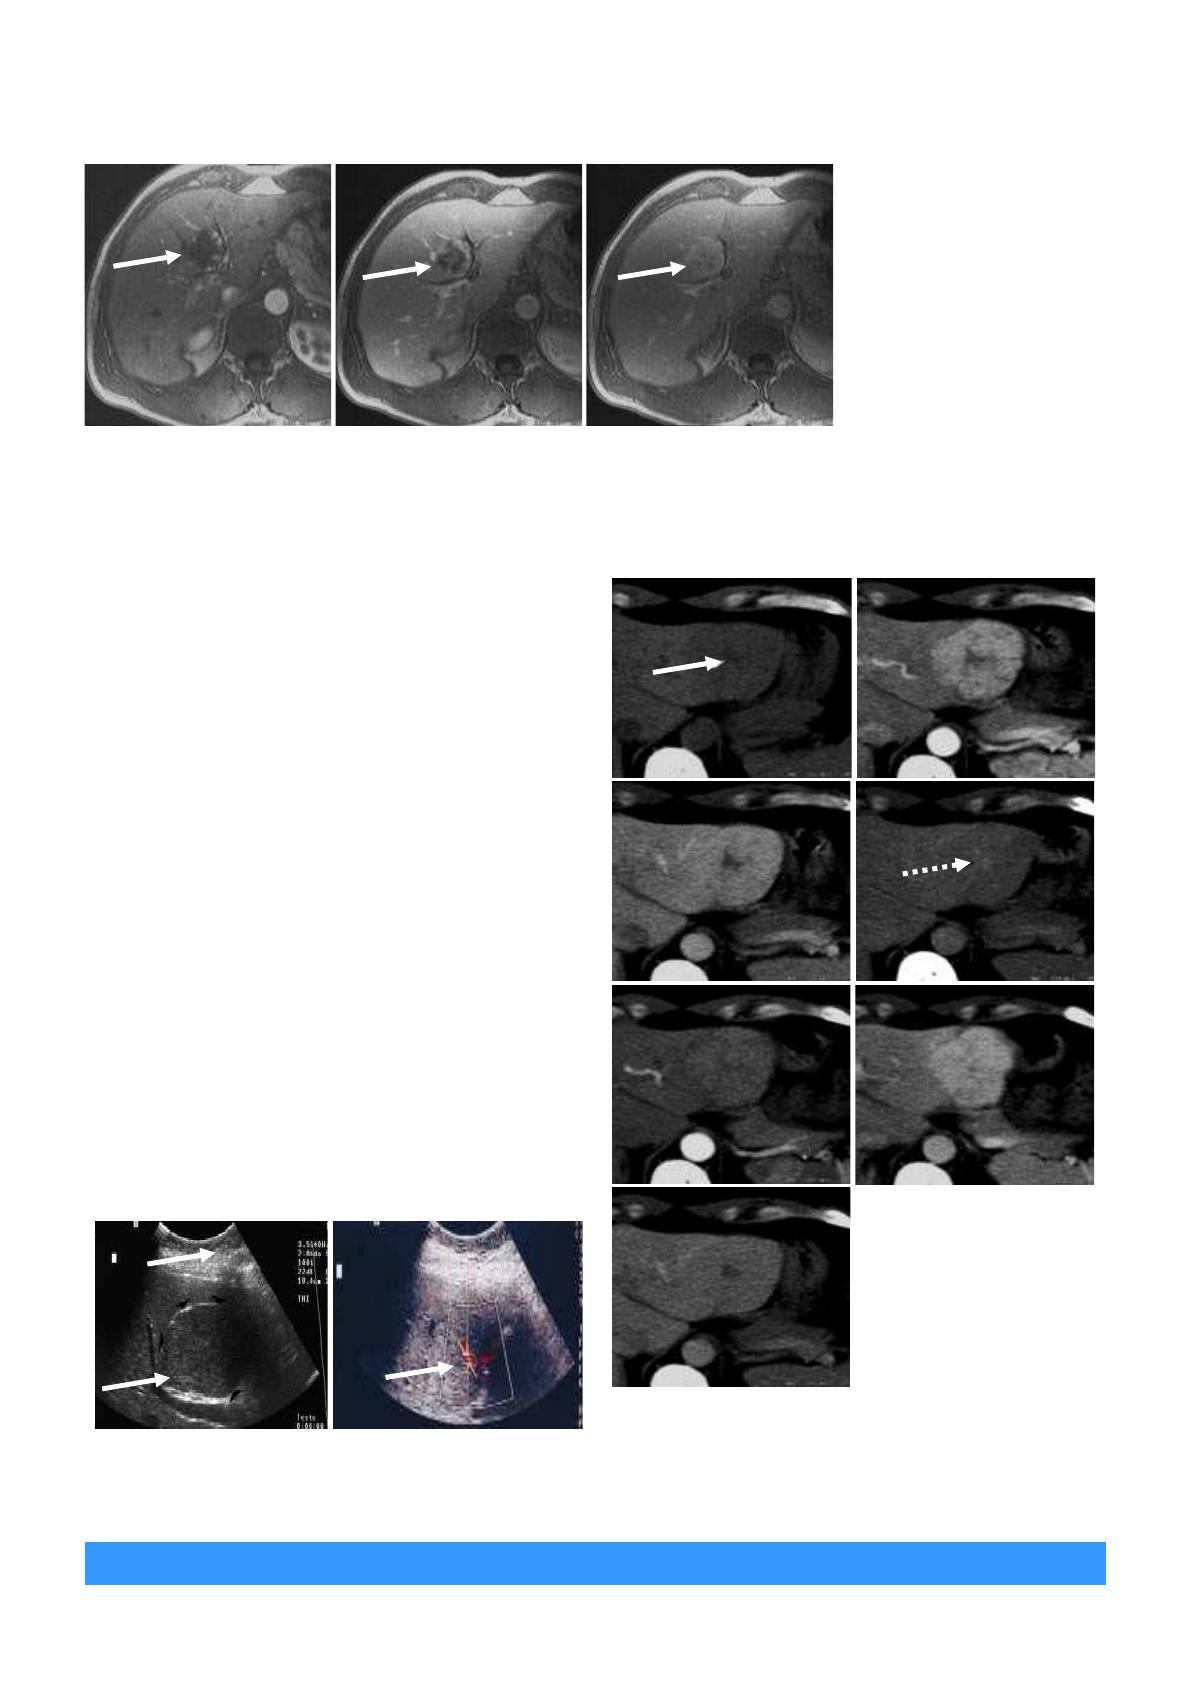

Figure 9.

Scanner hépatique au

temps artériel. Lésion avec une

hypervascularisée.